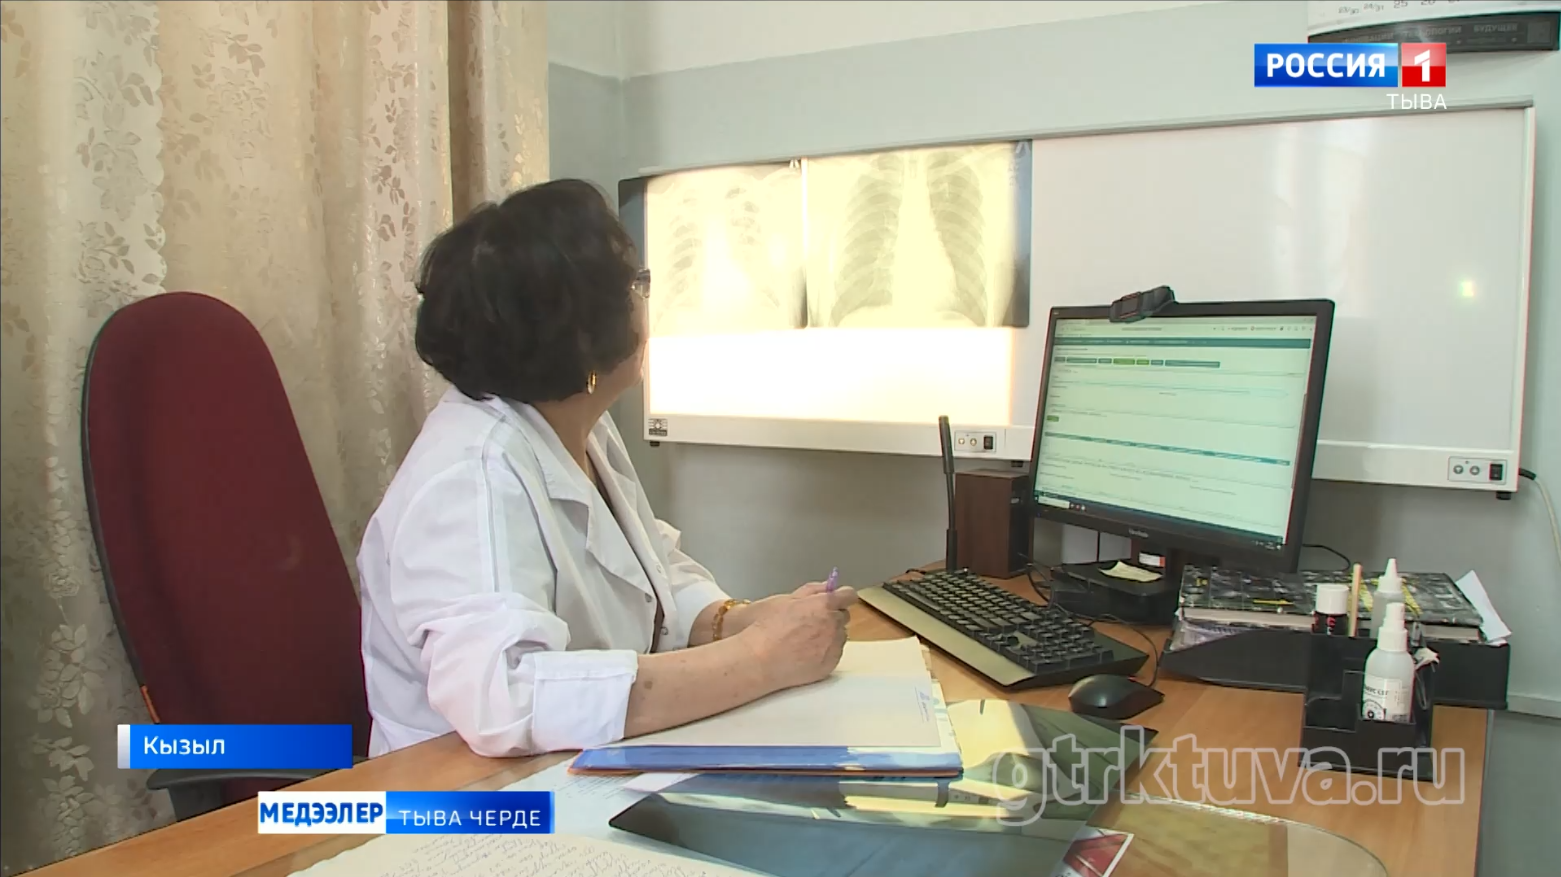

Тыва Россияда өкпе аарыының талазы-биле мурнуку одуругларда хөй чылдарның дургузунда чоруп орарын статистика көргүзүп турар. Социал аарыгларга хамаарыштырып турган туберкулез уе-шагның аайы-биле база өскерлип турар. Чогуур ужурлуг дериг-херексел, эм-таң-биле эмнелге хандыртынып турар. Удавас чаа оран-саваны база тудар. Эң кол чүве, аарыгны эмнээри берге-даа болза, үзе эмнеттинер, чүгле кижиниң бодунуң күзелинден хамааржыр. Аарыгны болдурбазы-биле профилактиканы чорудары чугула.

Март 24-те бүгү делегейде туберкулезка удур демисел хүнү. Аңаа тураскаадып, республикада өкпе аарыынга удур шалыпчы айны чарлаан. Фтизиатрлар көжүп чоруур мобильдиг хөрек тырттырар дерилгелиг автомашина-биле кожуун, сумуларны эргий кезип, найысылалдың аңгы-аңгы микрорайоннарынга чурттакчы чонну шинчилеп, көөр.